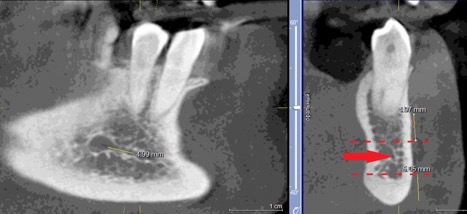

При измерении расстояния от резцовой петли до вестибулярной стенки нижней челюсти и её топографии в области правила «трёх пятёрок», выделено три положения канала, в котором проходит резцовая петля: канал прилежит, т.е. стенка канала образована кортикальной частью (рис 3), касается, т.е. имеет одну общую точку (рис 4) и не имеет общих точек.

Рисунок 4. КЛКТ Сагиттальныи и коронарныи реформаты переднего отдела нижнеи челюсти..jpg

Рисунок 4. КЛКТ Сагиттальный и коронарный реформаты переднего отдела нижней челюсти.

Канал соприкасается с кортикальной частью кости (красная стрелка – резцовая петля).